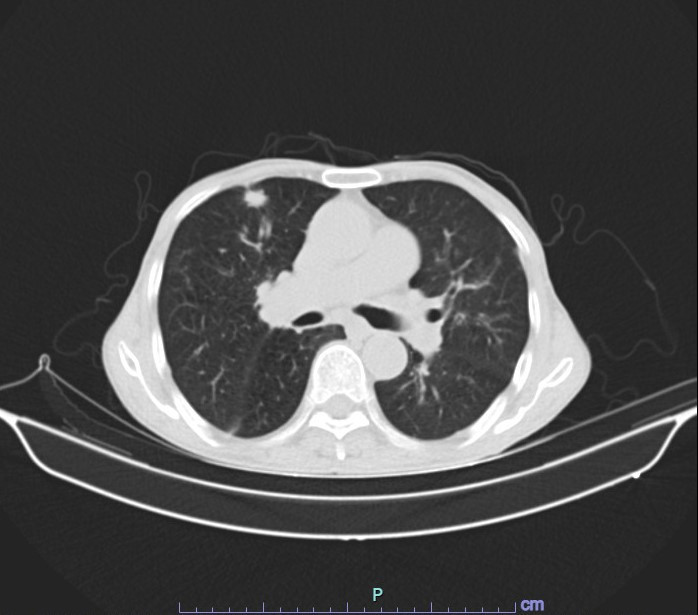

Mới đây nhất là trường hợp người bệnh Đ.V.L., 74 tuổi ở Phù Ninh, Phú Thọ nhập viện cấp cứu tại Khoa Nội hô hấp – Tiêu hóa trong tình trạng ho, khó thở. Các bác sĩ tại khoa đã tiến hành cấp cứu kịp thời và chỉ định chụp cắt lớp vi tính cũng như các cận lâm sàng cần thiết để đánh giá lại tình trạng sức khỏe của người bệnh.

![]() |

| Hình ảnh kết quả chụp cắt lớp vi tính của người bệnh Đào Văn Lập - Ảnh BVCC |

Kết quả chụp cắt lớp vi tính lồng ngực cho thấy phổi ứ khí phế nang, giãn phế nang. Chẩn đoán đợt cấp bệnh phổi tắc nghẽn mãn tính COPD trên nền người bệnh tăng huyết áp và xơ vữa mạch máu. Đáng nói là, người bệnh có tiền sử hút thuốc lá, thuốc lào lâu năm và đã phải nhập viện cấp cứu rất nhiều lần nhưng đến nay người bệnh vẫn không thể cai được thuốc lá.